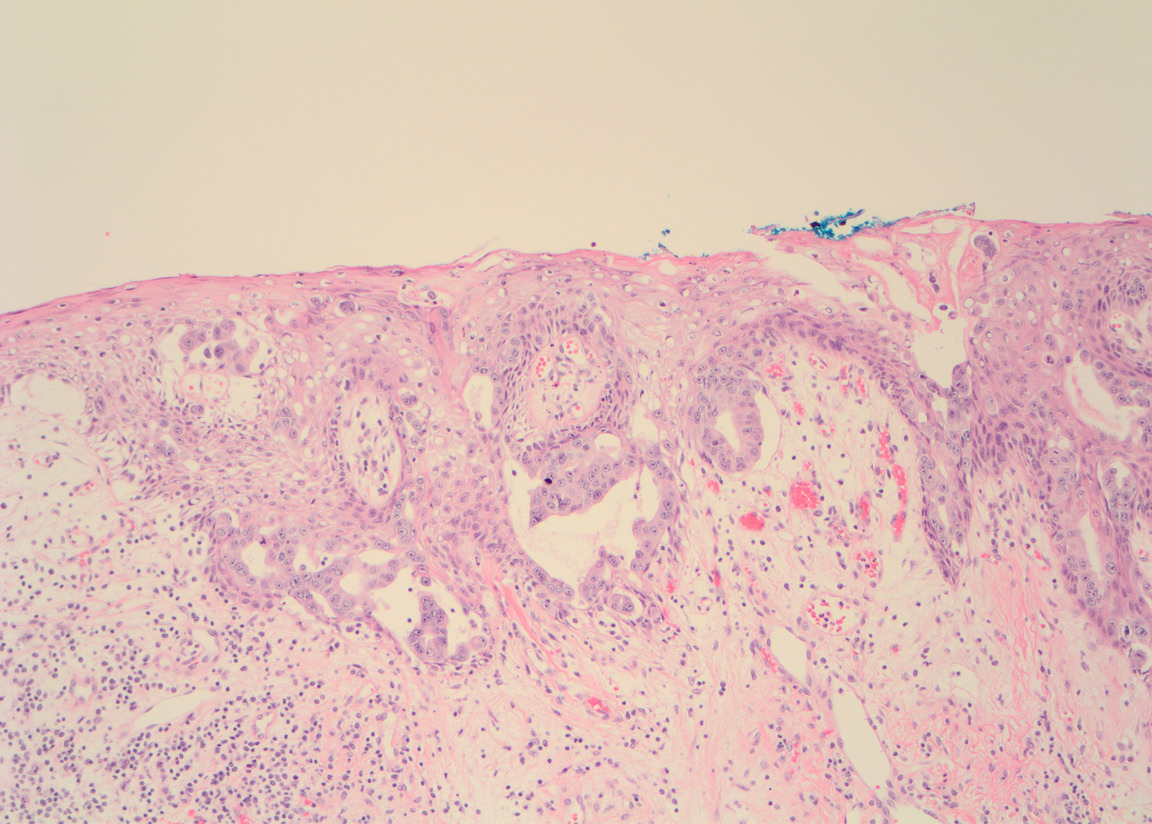

Microscopic (histologic) description

- Single cells or clusters of cells spread throughout the epidermis

- Cells have abundant pale cytoplasm, large irregular nuclei with prominent nucleoli

- Underlying dermis may have chronic inflammation

- Epidermis with hyperkeratosis and possibly ulceration

- Florid cases can show gland formation

- Paget cells may phagocytose melanin, mimicking melanocytes

- Underlying carcinoma is most commonly high grade invasive carcinoma of no special type (NST; 53 - 64%) or DCIS (24 - 43%) (Histopathology 2020;77:181)

Microscopic (histologic) images

Contributed by Anna Biernacka, M.D., Ph.D. and Mary Ann Gimenez Sanders, M.D, Ph.D.